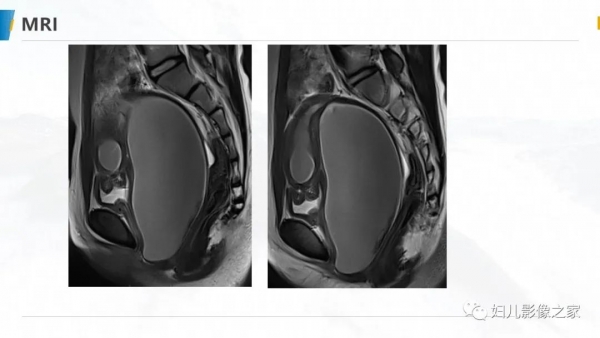

病例1

女,10岁,以“间断下腹痛7天”为主诉入院。入院查体:生命体征平稳, 心肺听诊无异常,腹软,肝脾未及,余无明显异常。

专科检查:外阴发育尚可,处女膜开口较小,棉签探入约4cm,无膨 隆,肛诊:子宫、宫颈膨隆,最低处距处女膜约4cm。

辅助检查:彩超(县中医院,2021-10-08):子宫体积增大,子 宫肌层变薄,内膜线消失,宫腔扩张,子宫颈管扩张,内充满大量液 性暗区,呈密集点状,阴道未见明显扩张。提示:1.胆囊内强回声2.胆 囊壁毛糙3.考虑处女膜闭锁。